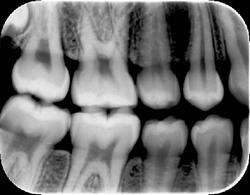

However, the human eye is only capable of distinguishing 32 shades of gray, which corresponds to a spatial frequency ranging from 5 to 7 lp/mm without magnification. The question then becomes, does the magnitude of a digital system spatial resolution above about 10 lp/mm make any diagnostic difference in the clinician’s ability to recognize pathosis radiographically? The answer is still being debated, but at least from our viewpoint, which can be supported from some of our initial investigations into this question, 1,2 probably not. Therefore as an example, can dentists recognize carious lesions confined to enamel as well using digital images as compared to radiographic film? Probably so, but further investigation is needed. An example of an image taken with a Soredex OpTime (spatial resolution of 12.5 lp/mm) is shown in Figure 1. An arrow is pointing to noncavitated proximal carious lesions.

Finally, overall appearance of the image can be a very subjective assessment. Most dentists prefer image appearance and definition to be as much like conventional film as possible. The bitewing image in Figure 2 was taken with a CCD sensor and the bitewing image in Figure 3 was taken with a Soredex OpTime PSP sensor using a dry skull to maximize the definition of bone. Both images were made using the same kV, mA, and time, using the same enhancement features of the particular post-processing software utilized by the imaging system. From a purely subjective viewpoint, some dentists may prefer one image over the other depending on their personal likes and dislikes.